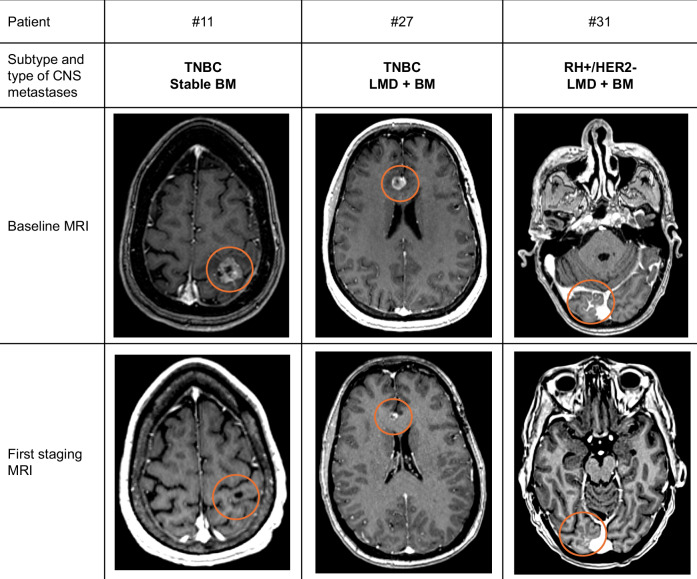

中枢神经系统(CNS)转移与转移性乳腺癌(MBC)患者预后不良相关。在这项回顾性研究中,我们研究了sacituzumab govitecan (SG)在33例her2阴性MBC和CNS转移患者中的活性,包括活动性、稳定性/治疗性和轻脑膜病(LMD)。在重度预处理人群中,SG显示中度中枢神经系统客观缓解率为4/30(13%),中位中枢神经系统无进展生存期为2.9个月(95%CI:2.0-4.3)。

Central nervous system (CNS) metastases are associated with poor prognosis in patients with metastatic breast cancer (MBC). In this retrospective study, we investigated the activity of sacituzumab govitecan (SG) in 33 patients with HER2-negative MBC and CNS metastases, including active, stable/treated, and leptomeningeal disease (LMD). SG demonstrated a modest CNS objective response rate of 4/30 (13%) and median CNS-progression-free survival of 2.9 months (95%CI:2.0-4.3) in a heavily pretreated population.